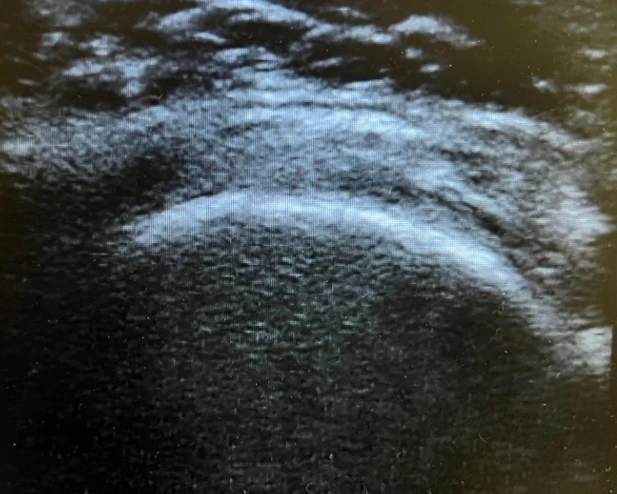

Διάγνωση

Ο ασθενής με με σύνδρομο υπακρωμιακής προστριβής του ώμου χρειάζεται εκτίμηση από εξειδικευμένο Ορθοπαιδικό Χειρουργό. Ο κ. Βλάχος αφού λάβει το ιστορικό σας και σας εξετάσει πολύ προσεκτικά, θα πραγματοποιήσει υπερηχογράφημα με σκοπό να ελέγξει την ακεραιότητα των τενόντων του στροφικού πετάλου. Επίσης θα χρειαστεί η λήψη μιας ακτινογραφίας ώστε να αποκλειστεί το ενδεχόμενο οστεοαρθρίτιδας ή άλλων παθήσεων του ώμου. Σε συγκεκριμένες περιπτώσεις ο ιατρός θα χρειαστεί να σας παραπέμψει για μαγνητική τομογραφία του ώμου.